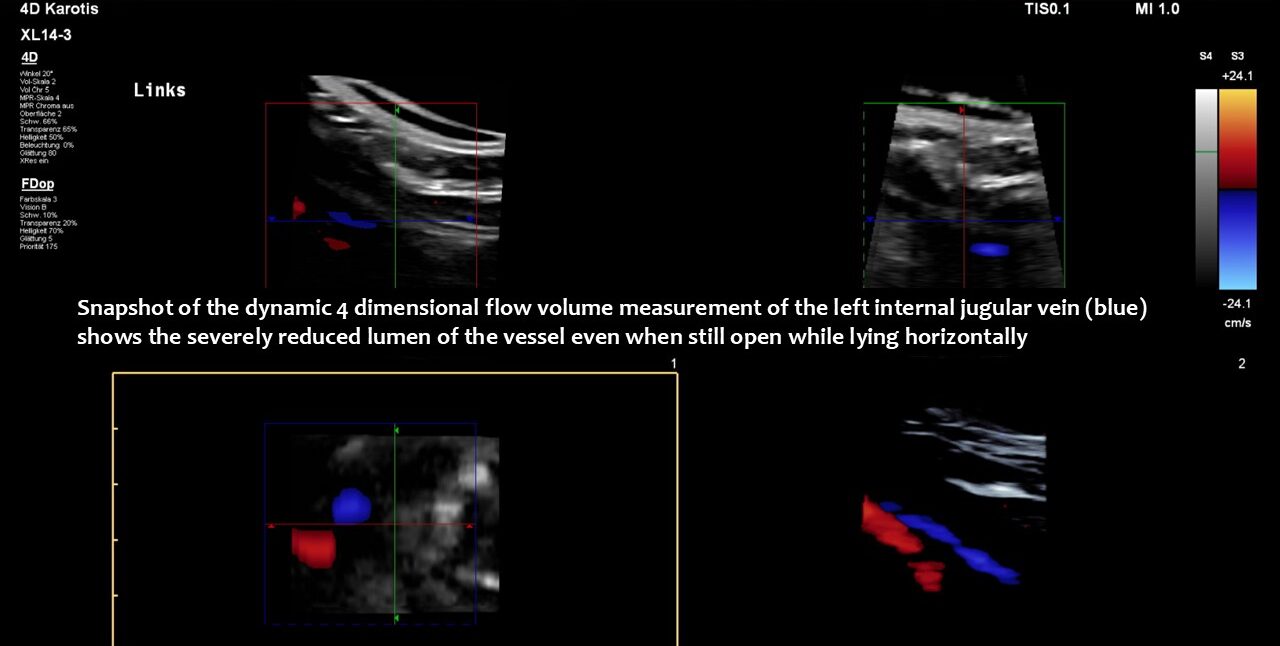

Consequently, blood had difficulty leaving the skull, resulting in continuously increased pressure and severe headaches, as well as other neurological dysfunction. The left side was more affected due to the double compression. This was clearly demonstrated by four-dimensional volume flow measurements in both jugular veins.

Only a four-dimensional volume flow measurement of the jugular veins can determine the cause of the daily headaches. The overall reduction in venous outflow from the brain in both jugular veins, totalling 258 mL/min, is significantly lower than the normal average volume of 719 mL/min. Consequently, the patient can eliminate only 36% of the required flow volume, while additional volume is forced into the skull from the left renal vein via the tronc réno-rachidien and from the left common iliac vein via the left ascending lumbar vein. This results in a chronic increase in intracranial pressure, as demonstrated by the elevated cerebrospinal fluid pressure obtained through a lumbar puncture. When the left jugular vein is also completely compressed due to increasing cervical lordosis when upright, the headaches become unbearable, accompanied by additional neurological symptoms as described by the patient.

Without this sophisticated technique, it would be unclear how severe the pressurization of the skull was and that, despite compression of both jugular veins, the right one was the main escape route from the skull.